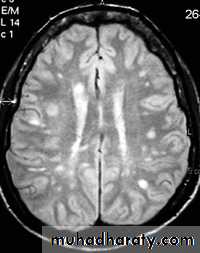

MULTIPLE SCLEROSIS:

-common neurological disorder.

-characterized by disseminated plaques of demyelination & gliosis throughout the neuraxis.

-MRI is more sensitive than CT in the demonstration of MS plaques.

- the most characteristic appearance is that of peri ventricular nodular Hyper intense lesions on T2 weighted images.

-the plaques are also well seen at the gray- white matter interfaces.

-some lesion may show a central area of greater signal intensity , resembling a target.

-contrast enhancement after giving gadolinium occurs in the acute phase indicating activity & in the chronic phase doesn't enhance.

SAGITAL FLUID ATTENUATION INVERSION RECOVERY SEQUENCE: OVOID PLAQUES ( HIGH SIGNAL INTENSITY) , WHICH ARE PERPENDICULAR TO LATERAL VENTRICLE.